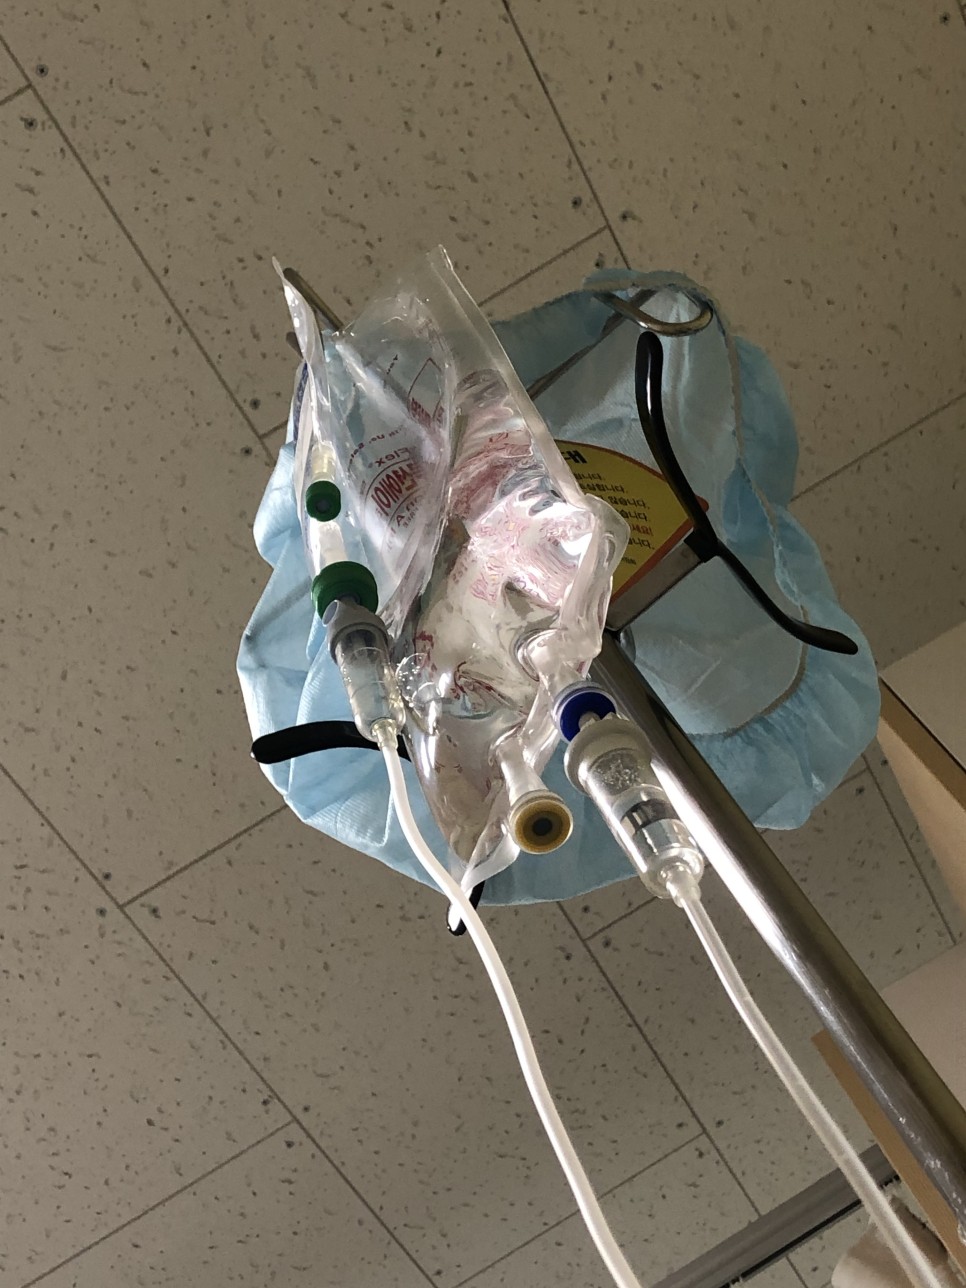

이 링거 주사 놓을 때 너는 정말 아팠어요….. 주사 바늘이 두껍대요 (´;ω;`)

저 부위는 입원 중 계속 뻐근한 기미

그리고 간호사가 계속 오셔서 열체크, 수액체크 등 합니다!